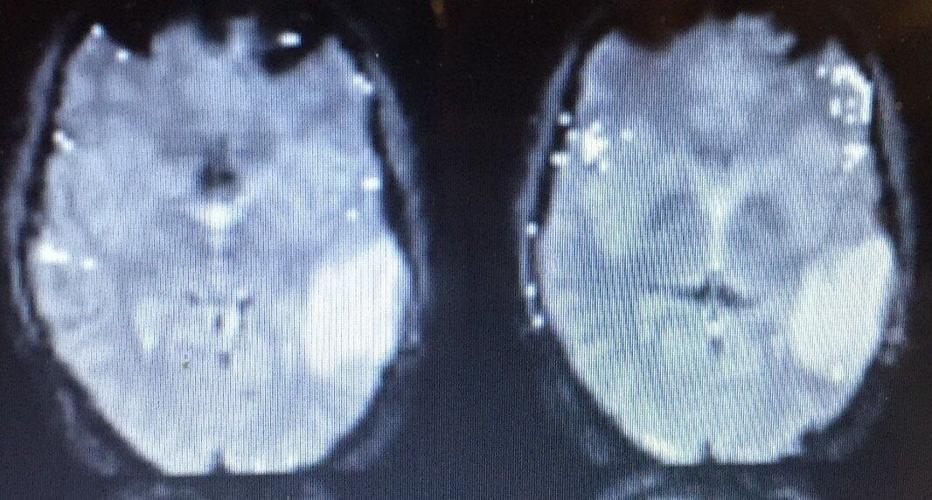

Ollie Knight's brain scans. (Brain Tumour Research via SWNS)

He was transferred to the National Hospital for Neurology and Neurosurgery in Queen Square, London for a craniotomy - the removal of part of the bone from the skull to expose the brain - and was later diagnosed with a grade 2 astrocytoma - a type of cancer that can occur in the brain or spinal cord.

Surgeons successfully removed 80 per cent of the tumor but three days later he suffered from a full tonic-clonic seizure and was later diagnosed with a grade 2 astrocytoma - a cancerous brain tumor with a poor prognosis, where 45 per cent of those live for five years or longer.